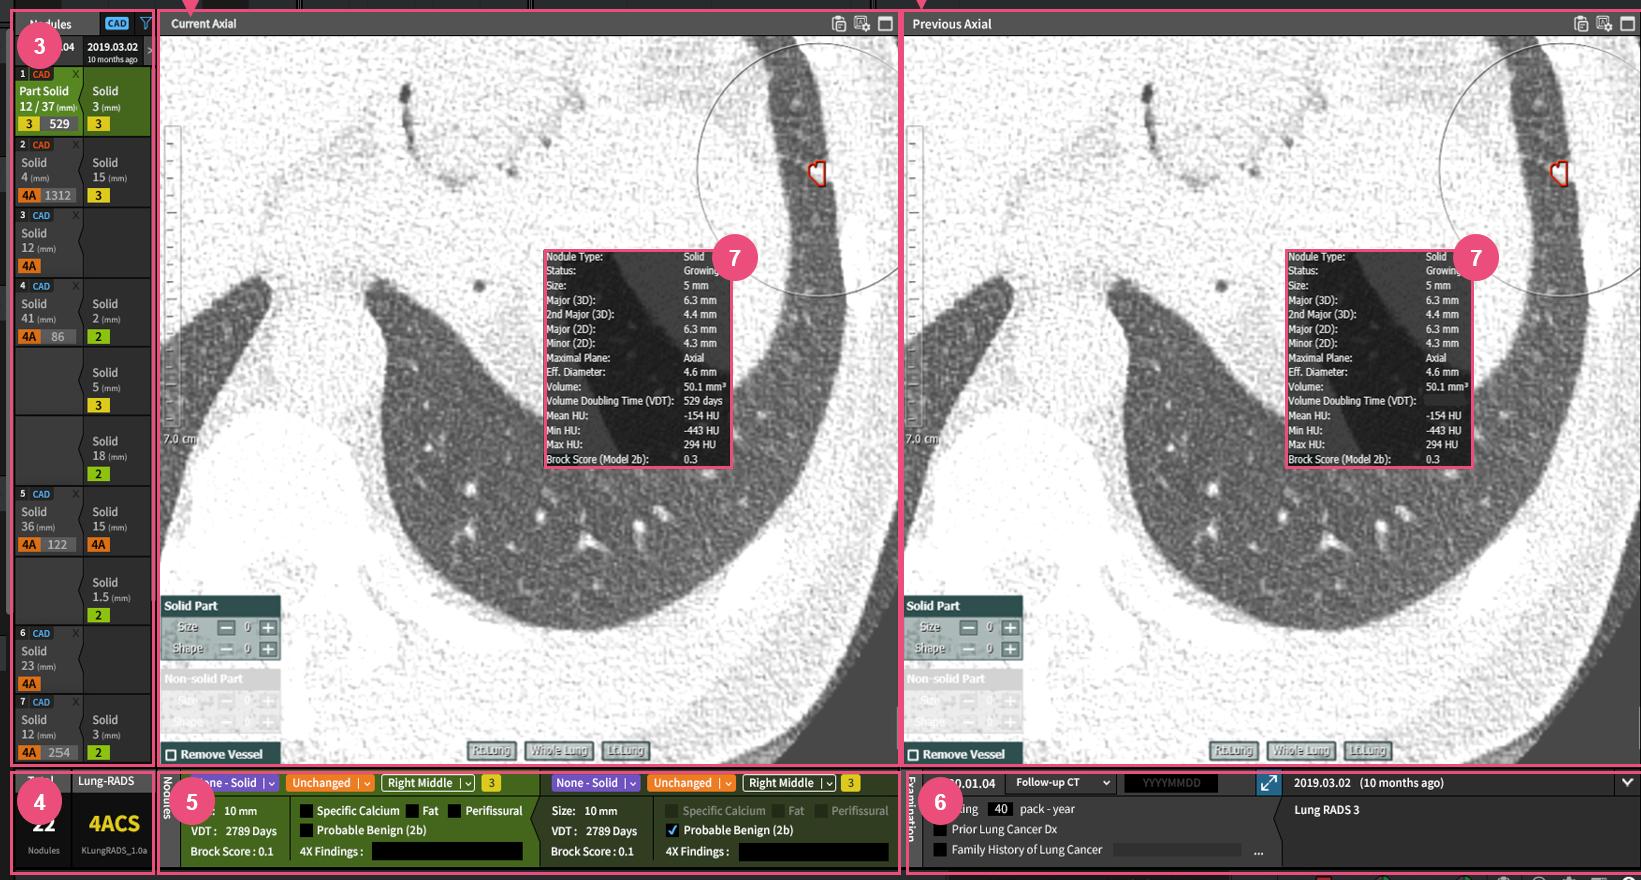

The PAIRR (Pulmonary Artificial Intelligence and Radiomics Research) Laboratory is a research unit of the Department of Radiology at UMass Memorial Medical Center and UMass Chan Medical School. Its mission is to develop, test, and implement innovative technology based on Artificial intelligence (AI) and Radiomics in the field of respiratory imaging.

The core research projects of the PAIRR Laboratory are based on accuracy and efficiency testing of novel AI and radiomics technologies. Additional research is focused on evaluating novel approaches to using these technologies, for example by combining or blending algorithms. Efficiency testing revolves around clinical algorithm implementation and the associated impact on work-flow and costs. Finally, a branch of research aims to develop and test mechanisms and metrics to quantify the “added-value” of novel technology to the clinical radiology workplace, and to analyze the increasing complexity of information generated by this technology.